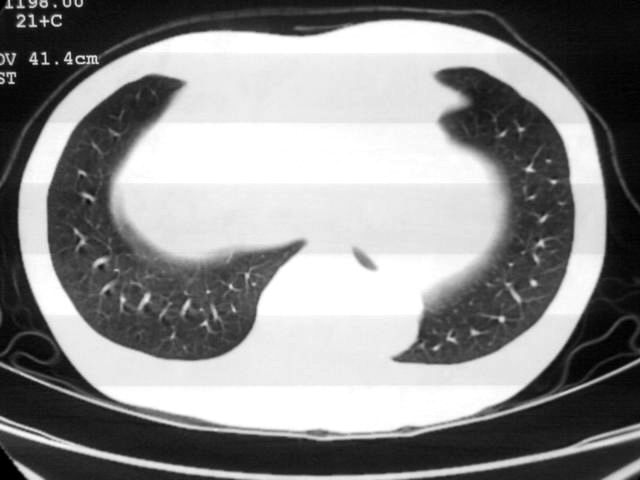

以下是引用苯小孩在2007-4-24 19:46:00的发言:[br]左下肺内侧基底段,见类圆形病灶,边缘清晰光滑.强化后轻中度强化.<平扫第4层面似有从腹主动脉相连血管影,可惜强化扫描这层没有抓住>考虑:左下肺隔离症.建议dsa或薄层强化重建观察.

以下是引用同在2007-4-24 20:11:00的发言:[br]考虑肺隔离症